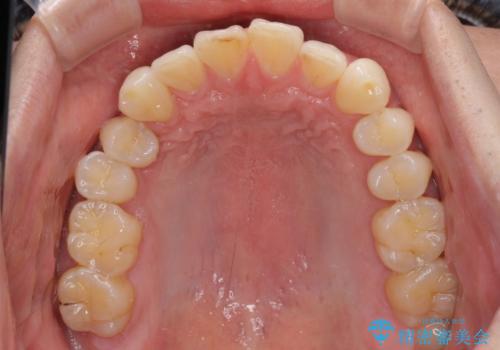

- 以前矯正治療を行ったものの、思い通りの仕上がりではなく、更には後戻りが気になってきたとのことで来院された患者様です。

上顎右側の第一小臼歯が動きにくい歯であり、以前矯正治療を行った際に傾斜した位置のまま終了したことと、それに伴い後戻りで歯列が波打っているようになっていることを大変気にしていらっしゃいました。

咬合平面改善のため、アンカースクリューを多用し、ワイヤー装置にて矯正治療を行うこととしました。

動きにくい歯はやはり動きにくく、咬み合わせ改善に時間を要しましたが、患者様には大変満足していただけました。